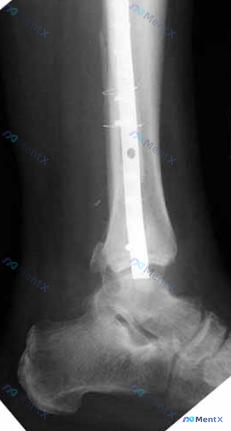

整理了一份最近看到的病例,觉得在术后早期评估上挺有警示意义,分享一下思路: 病例基本情况 - 患者:34岁女性 - 背景:左踝腓骨远端骨折行切开复位内固定(ORIF)术后3周 - 就诊原因:寻求第二医疗意见 影像关键点梳理(正位+侧位小腿X光) 先看影像报告给的客观表现: 1. 内固定物构成:不算少...